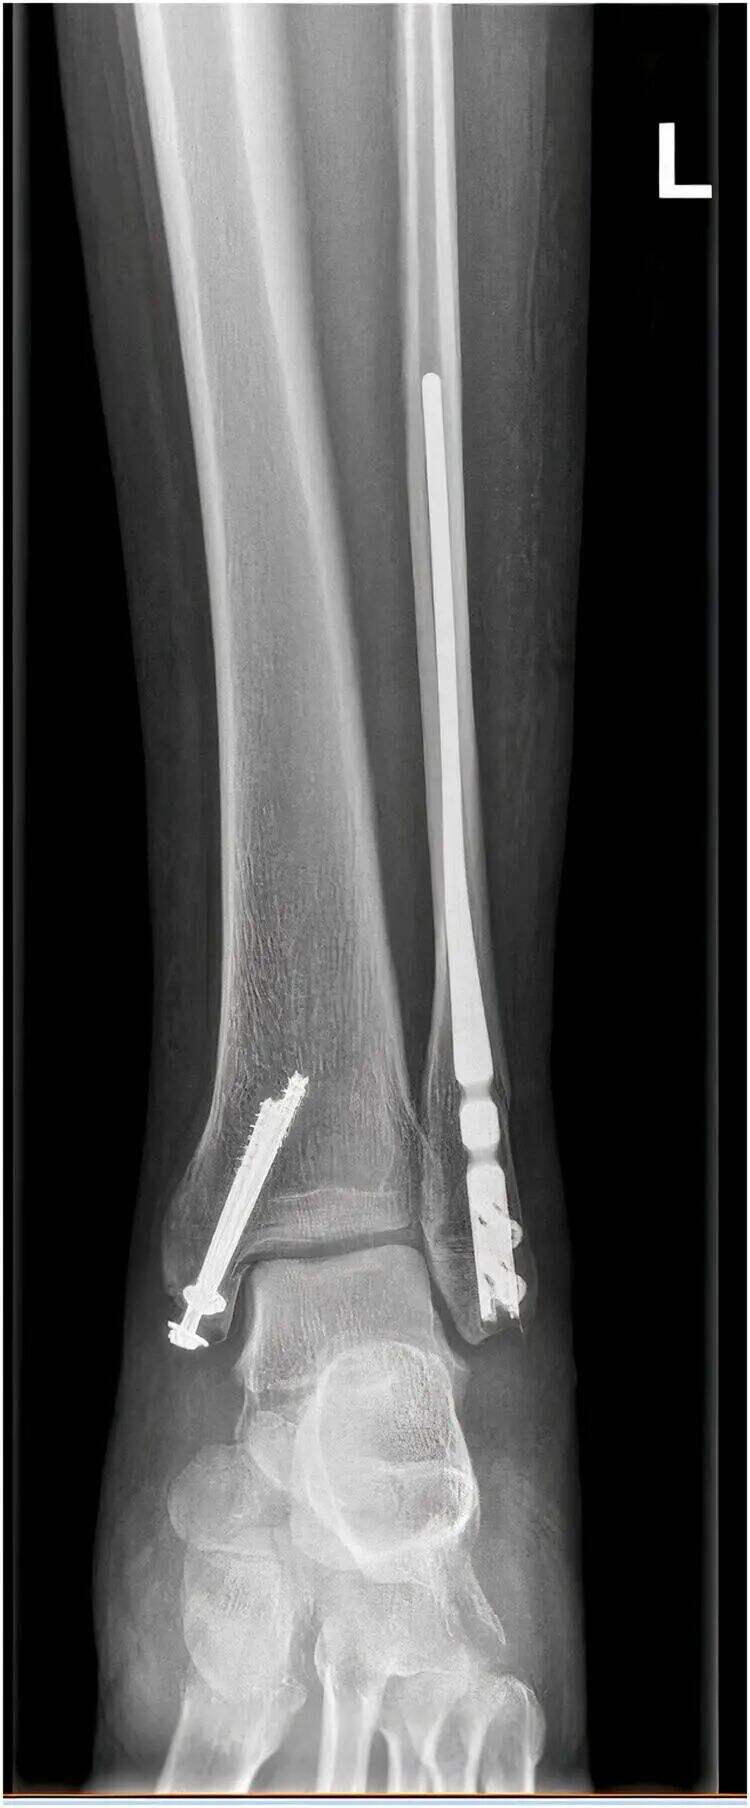

Az intramedullaris záró fibulaclips stabilizálja a distalis fibula töréseket hosszban és rotációban egy kis metszésen keresztül, lehetővé téve a distalis fibula törések minimálisan invazív kezelését. A fő clipp mellett az implantátum egy szindeszmotikus csavart is tartalmaz, amelyet kívülről befelé helyeznek be, valamint anteroposterior záró csavarokat, így elérve a „terhelésmegosztást”, amely korábbi betegmobilizációt tesz lehetővé. A minimálisan invazív megközelítés csökkenti az infekció és a rossz sebgyógyulás kockázatát is.

Ez a technika kiemeli az intramedullaris záró fibulaclipp optimális belépési pontját a redukció minőségének megfelelően, valamint a szindeszmotikus csavar beültetésének indikációit.

3. Ha a fenti lépések egyike sem eredményezi a kielégítő redukciót, akkor ajánlott egy kis metszés a törés helyén nyitott redukció céljából, ahogy az alábbi ábra mutatja.